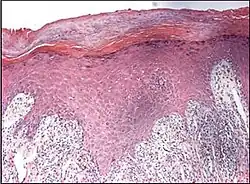

Interface dermatitis

These are sorted into either:[2]

- Interface dermatitis with vacuolar change

- Interface dermatitis with lichenoid inflammation

Interface dermatitis with vacuolar change

| Generally/Not otherwise specified | Typical findings, called "vacuolar interface dermatitis":[6]

|